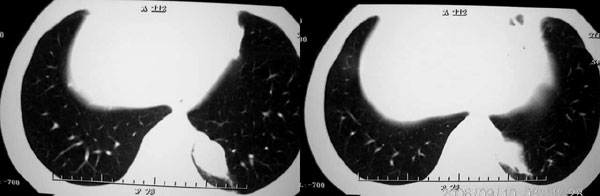

男 43 岁 左侧肩背部疼痛不适一个月,无畏寒 发烧 咳嗽.

左侧脊柱旁沟可见一边界清,密度不均匀之块状影,其内可见水样低密度影。

2、病变位于左肺下叶后段,周围肺组织相对干净,没有明显异常的改变,基本可以排除炎性病变;病变实质内密度均匀,边缘清晰,后下缘与膈脚分界不清晰。各征象均支持肺隔离症。